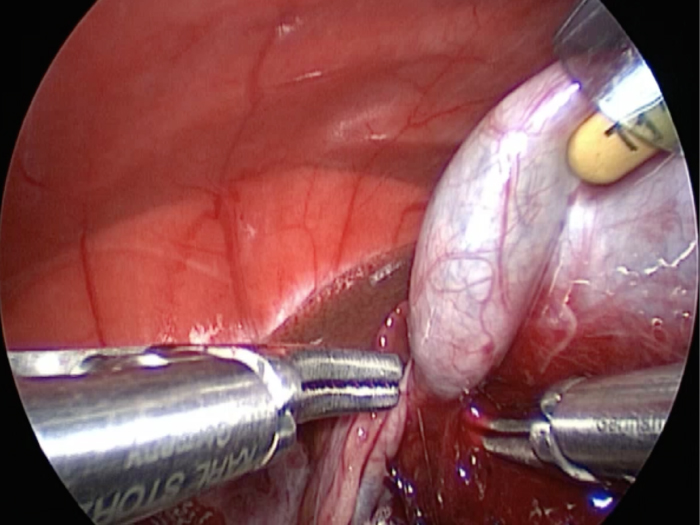

他院より紹介。胆嚢炎がひどく繰り返す嘔吐がありました。 腹膜と一部横隔膜に胆嚢ががっちりと癒着していました。 体重が2kgと体も小さかったのですが、飼い主さんの希望もあり、腹腔鏡下で手術を実施することになりました。

丁寧に丁寧に出血をコントロールしながら少しずつ手術をすすめていきます。

癒着(矢印)がひどく胆嚢を確認することができませんでした。

このように癒着しているときはギリギリで剥がすとひどく出血をおこすことがあるので無理にはがそうとしないで、脂肪の血管に注意しながら脂肪ごと剥がしていきます。